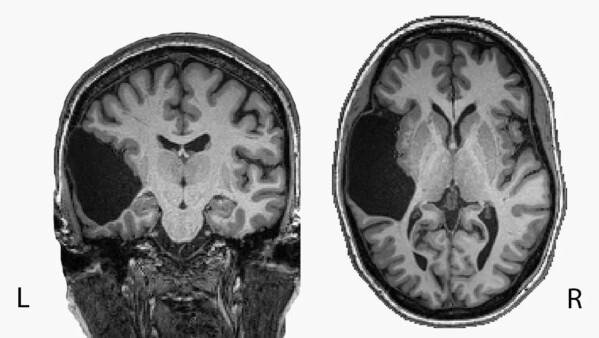

Пациентка впервые узнала, что её мозг нетипичен, уже в зрелом возрасте, когда ей сделали его сканирование по несвязанной с этим причине. Вероятно, в детстве она перенесла инсульт: сейчас в этой области мозга находится только спинномозговая жидкость.

У большинства людей преимущественная часть языковой обработки происходит в левом полушарии мозга, у некоторых нагрузка распределяется поровну между двумя полушариями, ещё реже правое полушарие берет на себя большую часть задачи. Обработка речи в основном происходит в двух основных частях мозга: лобной и височной областях. Первыми развиваются височные доли, а к пяти годам — лобные.

Учёные до этого не знали, могут ли формироваться лобные доли в отсутствие височных, но опыт пациентки Федоренко показал, что могут. Серия экспериментов подтвердила, что её языковые способности ничуть не уступают таковым у нейротипичных людей.